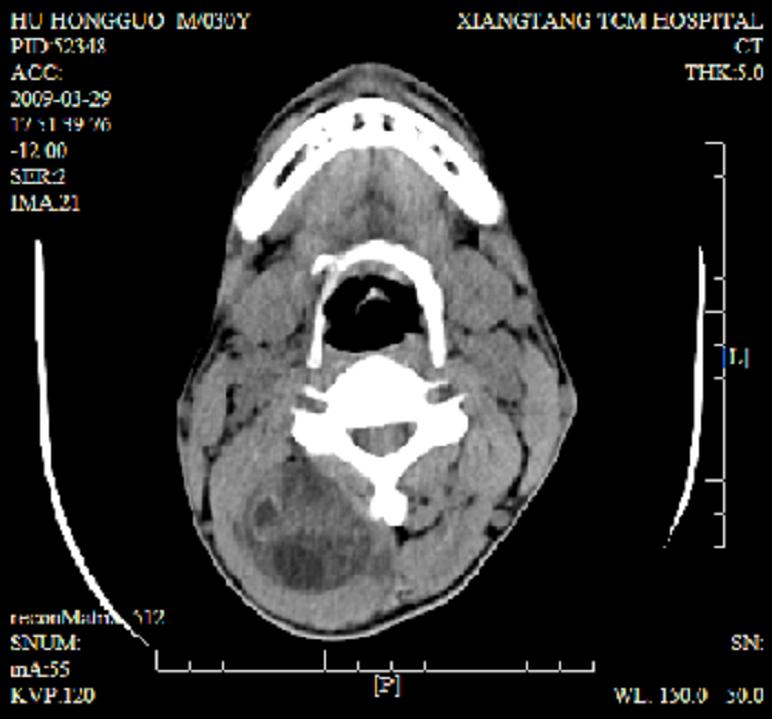

标题: CT19102:颈部肿块

男30y发现肿块3年

多处囊实性肿块,形态欠规则有一定形态,内见点状钙化,以囊变为主,增强后轻度强化,首先考虑神经源性肿瘤如鞘瘤,不除外脉管源性肿瘤如淋巴管瘤(见缝钻及囊性区域太多,如果合并感染完全可以这个影像表现),和海绵状血管瘤,但是血管瘤不太支持因为强化特征和病灶形态不典型.

右侧椎前间隙后部肌间、皮下囊性为主病变,可见分隔和点状钙化,分隔和壁呈轻度环形强化,大部分无强化。形态不规则,有钻缝特点。考虑1 淋巴管瘤合并感染2 血管平滑肌脂肪瘤3 表皮样囊肿4 不除外海绵状血管瘤。